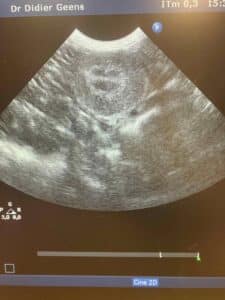

Un chat de 13 ans est venu pour vomissements. Comme il est maigre et qu'il boit un peu plus, j'ai proposé une échographie. Le rein a une apparence anormale, il est hyperéchogène, ce qui fait penser à une néphrite. Une prise de sang effectuée a permis de confirmer une insuffisance et une infection rénales , un traitement a pu être instauré le soir même.